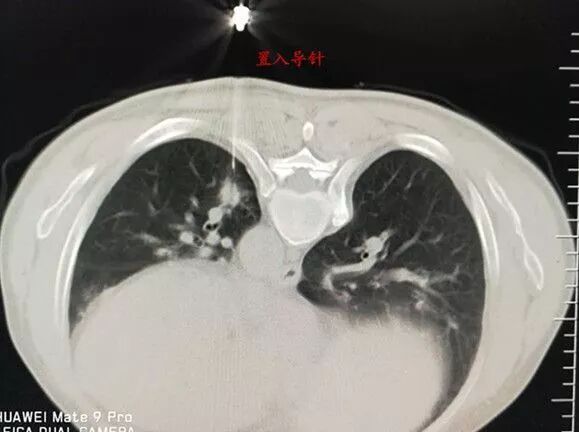

選擇右成角入路,穿越胸骨與主動脈間隙,該間隙僅僅10mm,并避開右胸廓內動脈,精細操作,先置入導針

再置入16G切割活檢槍,稍有偏差便可導致升主動脈損傷破裂,導致災難性后果發(fā)生。